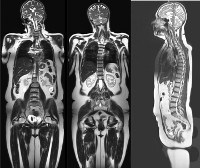

МРТ всего тела. Диагностическая методика, позволяющая визуализировать все анатомические зоны организма человека в одном исследовании. Процедура основана на явлении ядерного магнитного резонанса. Метод наиболее часто используется в процессе поиска рака. В некоторых случаях методика применяется при обширных локальных поражениях или системных заболеваниях. Кроме того, МРТ всего тела назначается в качестве профилактического обследования и в сложных случаях из-за трудностей с определением расположения патологических очагов различного происхождения. Эта диагностическая процедура востребована в онкологии, травматологии, ревматологии, неврологии, сосудистой хирургии и некоторых других областях медицины.

МРТ всего тела позволяет исследовать строение и расположение внутренних органов и различных анатомических структур, определять местоположение, характер и распространенность патологических вспышек, оценивать взаимосвязь между нормальными тканями и патологически измененными участками. МРТ всего тела включает визуализацию головного мозга, всех отделов позвоночника, органов грудной клетки (легких, средостения, плевры, скелета костей), органов брюшной полости и забрюшинного пространства (желудка, тонкой кишки и толстой кишки, печени, селезенки, поджелудочной железы, почек), органов таз (прямая кишка, мочевыводящие пути, мужские и женские половые органы), мягкие ткани и структуры твердых конечностей.